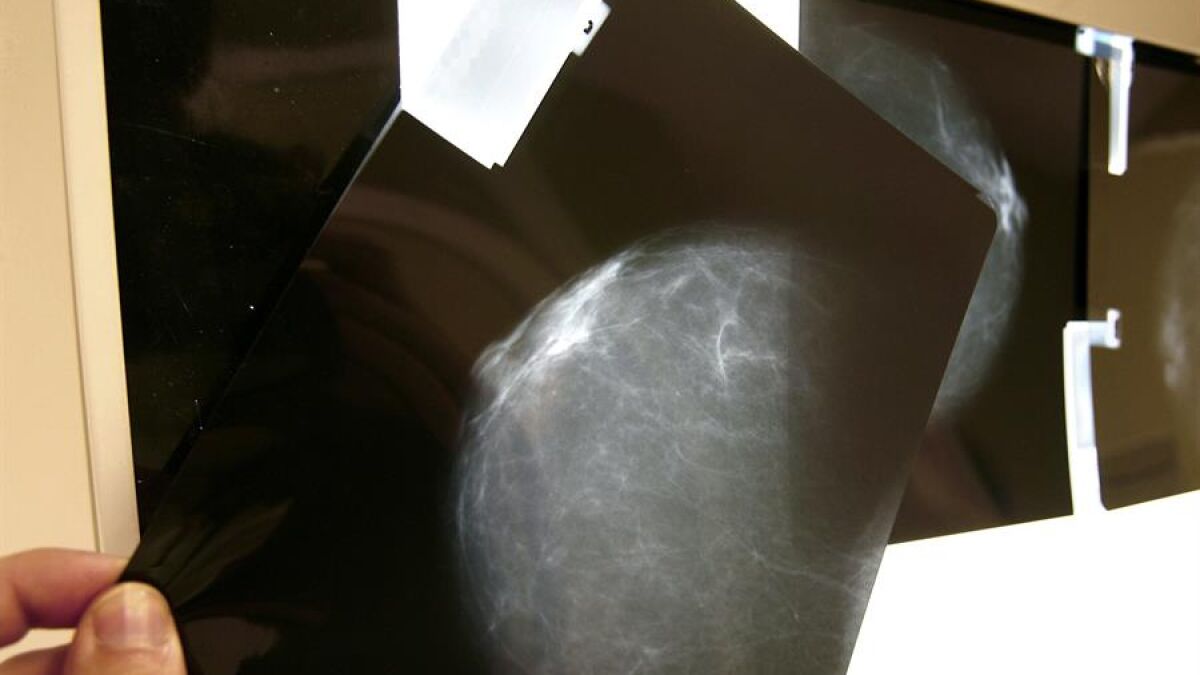

La mujer, de 45 años, acudió en marzo al Hospital de Requena donde, según se desprende de la demanda, refirió tumor en mama izquierda y antecedentes familiares. Sin embargo, no se le practicó mamografía ni ecografía ni RMN bilateral. Cuando regresó a revisión en junio tampoco fue remitida para que se le tomara ninguna muestra y, un mes más tarde, se le envió a su domicilio sin exploración radiológica alguna. En septiembre de ese año la mujer fue atendida en Urgencias por la aparición de un nódulo en mama aunque no fue hasta octubre cuando se le hizo una biopsia y se le comunicó el cáncer.

El TSJ determina un retraso de cinco meses

El tribunal estima que hubo un retraso en el diagnóstico pero desde junio y no desde marzo, tal y como mantenía la paciente. Al respecto, expone que pese a que la mujer dice que en marzo refirió tumoración tras notarse en autopalpación un bulto en el pecho en enero y que tenía antecedentes familiares, en el expediente consta que acudió al médico por dolor en mama sin antecedentes y sin que alcanzase a identificarse ninguna lesión palpable o signos de mastitis.

Se le practicó entonces ecografías en ambas mamas a la mujer, que se hallaba en lactancia materna y se le pautó control ecográfico en tres meses. Esta actuación, a juicio del tribunal, no resulta en modo alguno reprochable. Pero sí ve inadecuada la actuación sanitaria en los meses de junio y julio, cuando se mantiene el seguimiento con control ecográfico por identificarse un único quiste que se vació con una punción. En este punto, el tribunal advierte de que al observarse crecimiento y cambio de las características del quiste respecto a marzo, "resultaba adecuada la biopsia del mismo", tal y como también recogía la Administración en su contestación a la demanda cuando dijo que la biopsia quedaba restringida a casos en los que se observaba un crecimiento o cambio en las características del quiste.